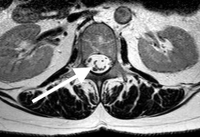

Arachnoiditis is actually the inflammation of the arachnoid membrane. The nerves are coated by this membrane within the CSF and inflammation can cause scarring and the nerves to “stick together” in clumps. Interestingly enough- like many conditions of the spine, some people have this condition and never develop symptoms.

The pathology of arachnoiditis of the lumbar spine is that the small spider web connections scar, contract and stick the nerves together. This reduces the nerve membrane exposure to the CSF and injures the small blood vessels that line and feed these nerves. This lack of blood circulation and the direct scar injury to the nerve can cause chronic nerve discharge or blocked signals. The nerves also don’t move normally when scarred. A normal nerve moves back and forth in the canal up to an inch when the leg is flexed or extended just like a cable over a pulley. If the nerve is tethered, it can’t stretch and the mechanical deformation with movement can cause symptoms.